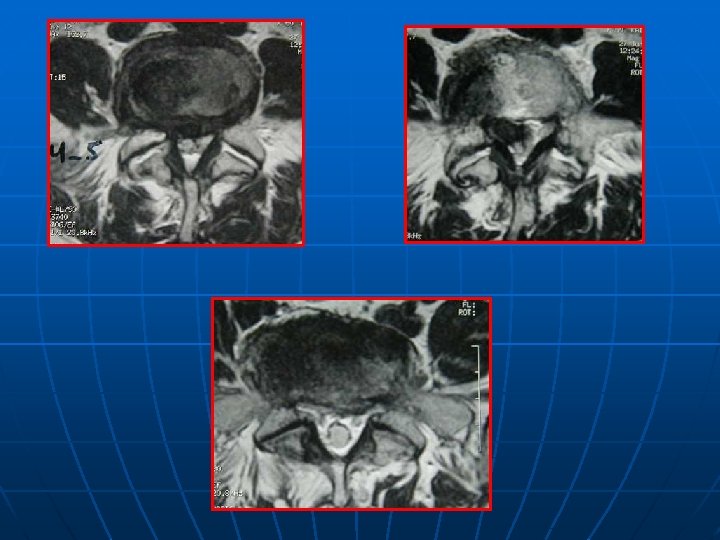

IRM n n EXAMEN CLE INCONVENIENTS : * statique * scoliose plan de coupe différent pour les étages STENOSE : centrale, foraminale ou associée (intérêt des coupes latérales foraminales) STRATEGIE OPERATOIRE+++ : ° état des disques (Modic? ) ° direction interligne articulaire : déstabilisation postopératoire?

SPONDYLOLESTHESIS ISTHMIQUE Rx standard: face+profil+3/4 D-G Découverte au stade de déplacement n Lombalgies isolées: pas d’autres explorations n Lombosciatiques: Rx dynamiques+ grand format+IRM ( TDM peu d’apport) n

CONCLUSION n n LOMBALGIES ISOLEE: Rx standard RADICULALGIES: Rx dynamiques, grand format, IRM: étude du disque sus jacent pour l’étendue de l’arthrodèse